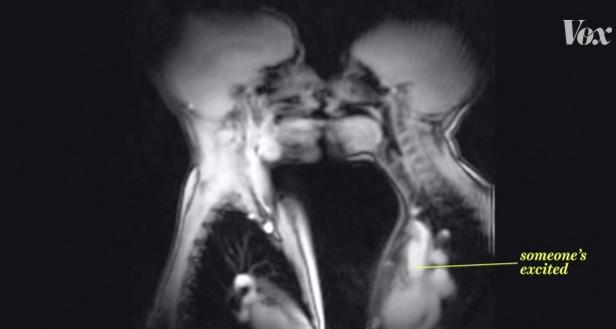

Ever wondered what goes on within the body when you are engaged in intercourse? With this Not suitable/safe for work (NSFW) video posted by VOX featuring footage from various MRI scanners allow for viewers to get a glimpse of what goes on inside the human body as it engages in activities from drinking pineapple juice to full-bore coitus.

The MRI movie shows how the tongue of a horn player moves and demonstrates how the heart starts beating faster when someone's excited, for example, while kissing, and how it is the uvula that moves when someone speaks German and it is the vocal chords that are put to use while speaking Chinese.

In another video posted on YouTube in February 2013, the first-ever recorded passionate French kiss of a couple in an MRI scanner at 3 Tesla magnetic field strength, the fast beating of the hearts can be clearly seen along with the movement of the tongues.